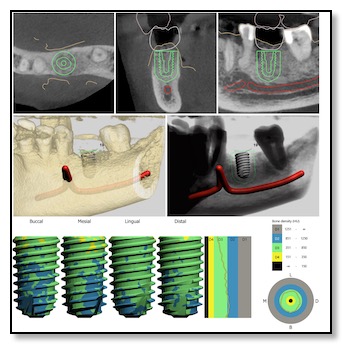

Surgical Guide Design

Patients often ask, "How does Dr. Tsai figure out exactly where to place the dental implant in my jawbone?" In the past, it relied a lot on the dentist's experience and judgment, as they would slightly pull back the gum tissue to assess the situation.

But thanks to recent advancements in digital dentistry, things have changed. Dr. Tsai is one of the few dentists in the Bay Area who has an in-house CT scanner (3D X-ray) and a 3D digital impressions camera.

She combines these technologies with a 3D printer. Here's how it works: she creates a digital model of your jawbone structure and overlays it with a 3D scan of your teeth and gums. Then, she aligns it with your natural bite to evaluate your biting and chewing patterns. This helps her determine the best position for the dental implant.

After this process, she collaborates with her lab to 3D print a template that acts as a guide for placing the implant with utmost precision regarding depth, angle, and location.

Designing this surgical guide is a meticulous process that usually takes about three weeks. It's especially crucial for all-ceramic dental implants, as well as standard ones.